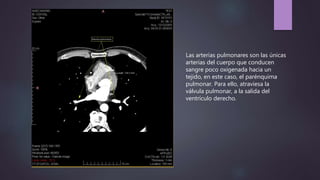

Las arterias pulmonares son las únicas

arterias del cuerpo que conducen

sangre poco oxigenada hacia un

tejido, en este caso, el parénquima

pulmonar. Para ello, atraviesa la

válvula pulmonar, a la salida del

ventrículo derecho.